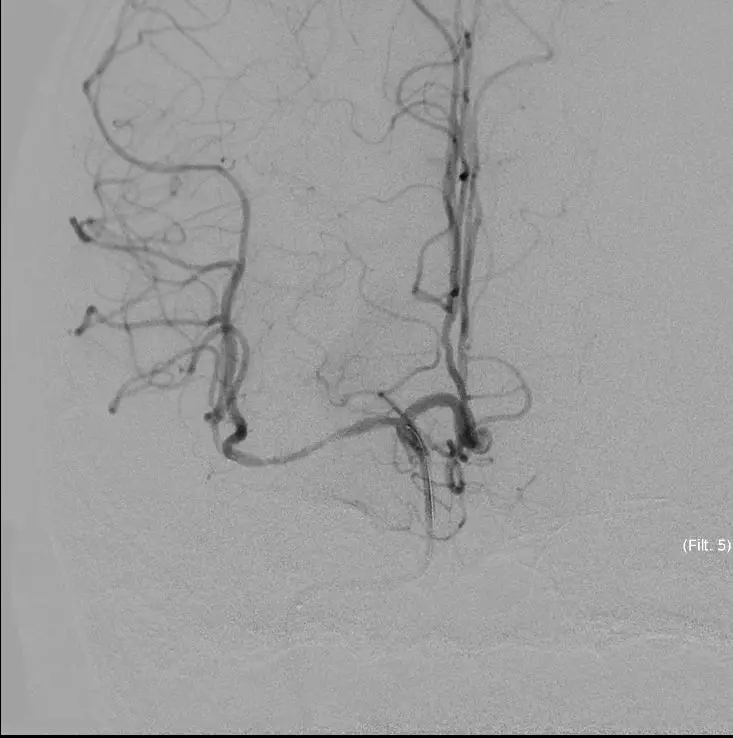

手术结束

持续替罗非班4ml/H静脉泵入

术后即刻复查头颅CT(17:33分)